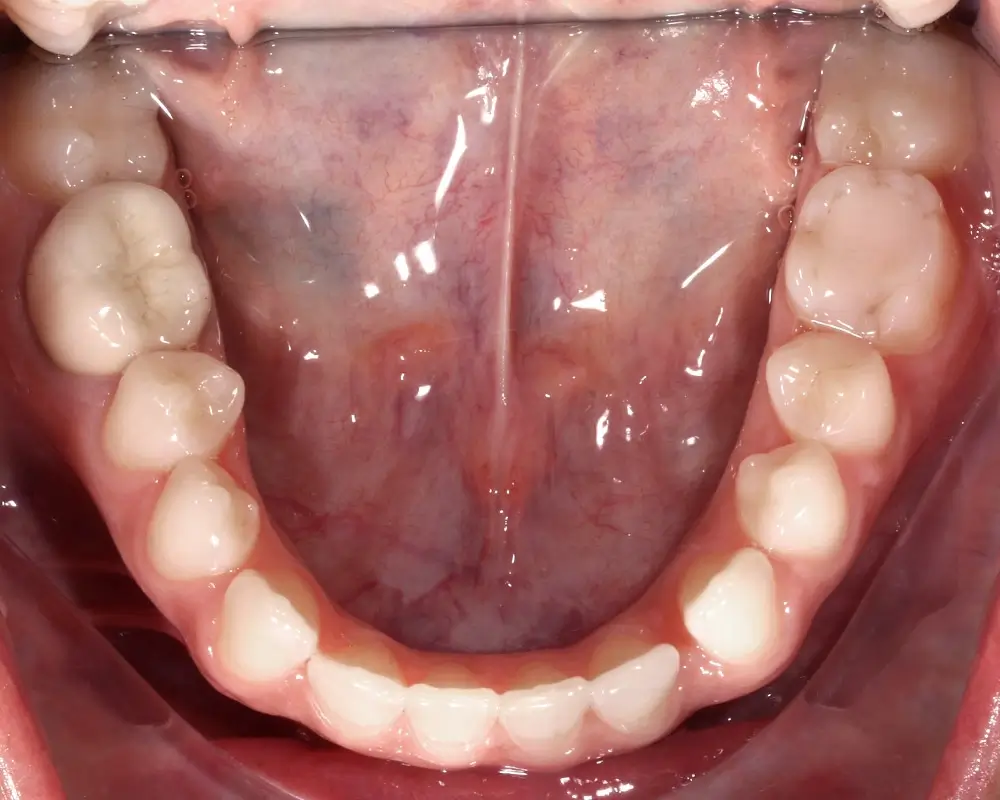

Открытый прикус - Кейс 5

Эффективность устранения дефекта прикуса посредством элайнеров FlexiLigner.

20

Количество кап НЧ

16

Количество кап ВЧ